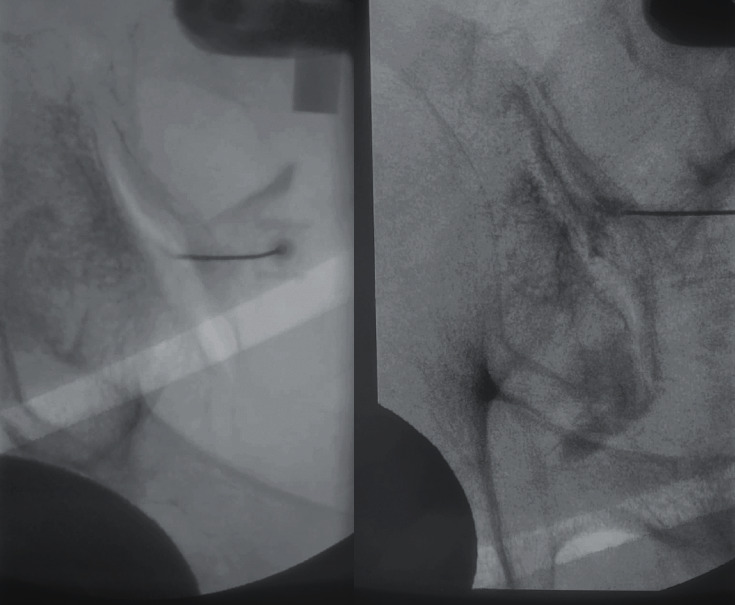

Percutaneous SI Joint Fusion

• iFuse (SI-BONE): Triangular titanium implants placed percutaneously across the SI joint under fluoroscopic guidance

• Approach: Lateral approach through the ilium into the sacrum